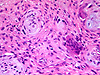

CASO N° 4 (Dr. Bonan e Dr. Roman)

Paciente do gênero masculino, 46 anos de idade, apresenta lesão no palato.